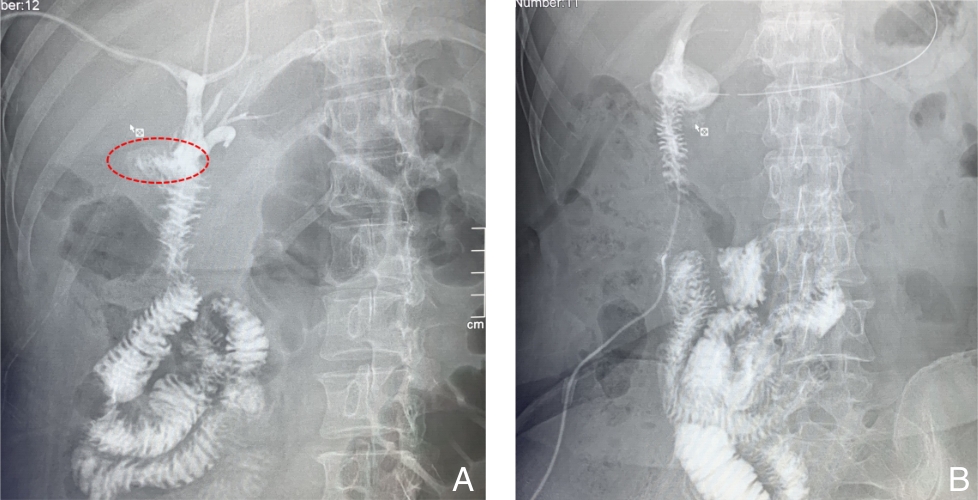

摘要:医源性胆管损伤(IBDI)是常见的胆管损伤类型,多发生于胆囊切除术。随着腹腔镜胆囊切除术的普及,其发生率明显高于开腹手术,且合并血管损伤(VI)的复杂病例逐渐增多,增加了诊治难度,严重时可导致肝缺血及萎缩。肝管空肠吻合术是胆管损伤后常用的重建方式,若合并VI,则可能需行肝切除。本文报告笔者收治的1例53岁女性患者,因胆囊切除术后出现胆汁漏入院。经2次多学科团队(MDT)讨论,术前评估显示肝右动脉及门静脉分支损伤并伴右前叶萎缩。根据术中所见,最终实施右半肝切除联合左肝管空肠Roux-en-Y吻合术。患者术后恢复顺利,随访6个月无明显不适。通过对该病例的诊治过程及文献的回顾与分析,本文总结了复杂IBDI的临床特点、诊治策略及MDT模式的价值,以期为临床实践提供借鉴。